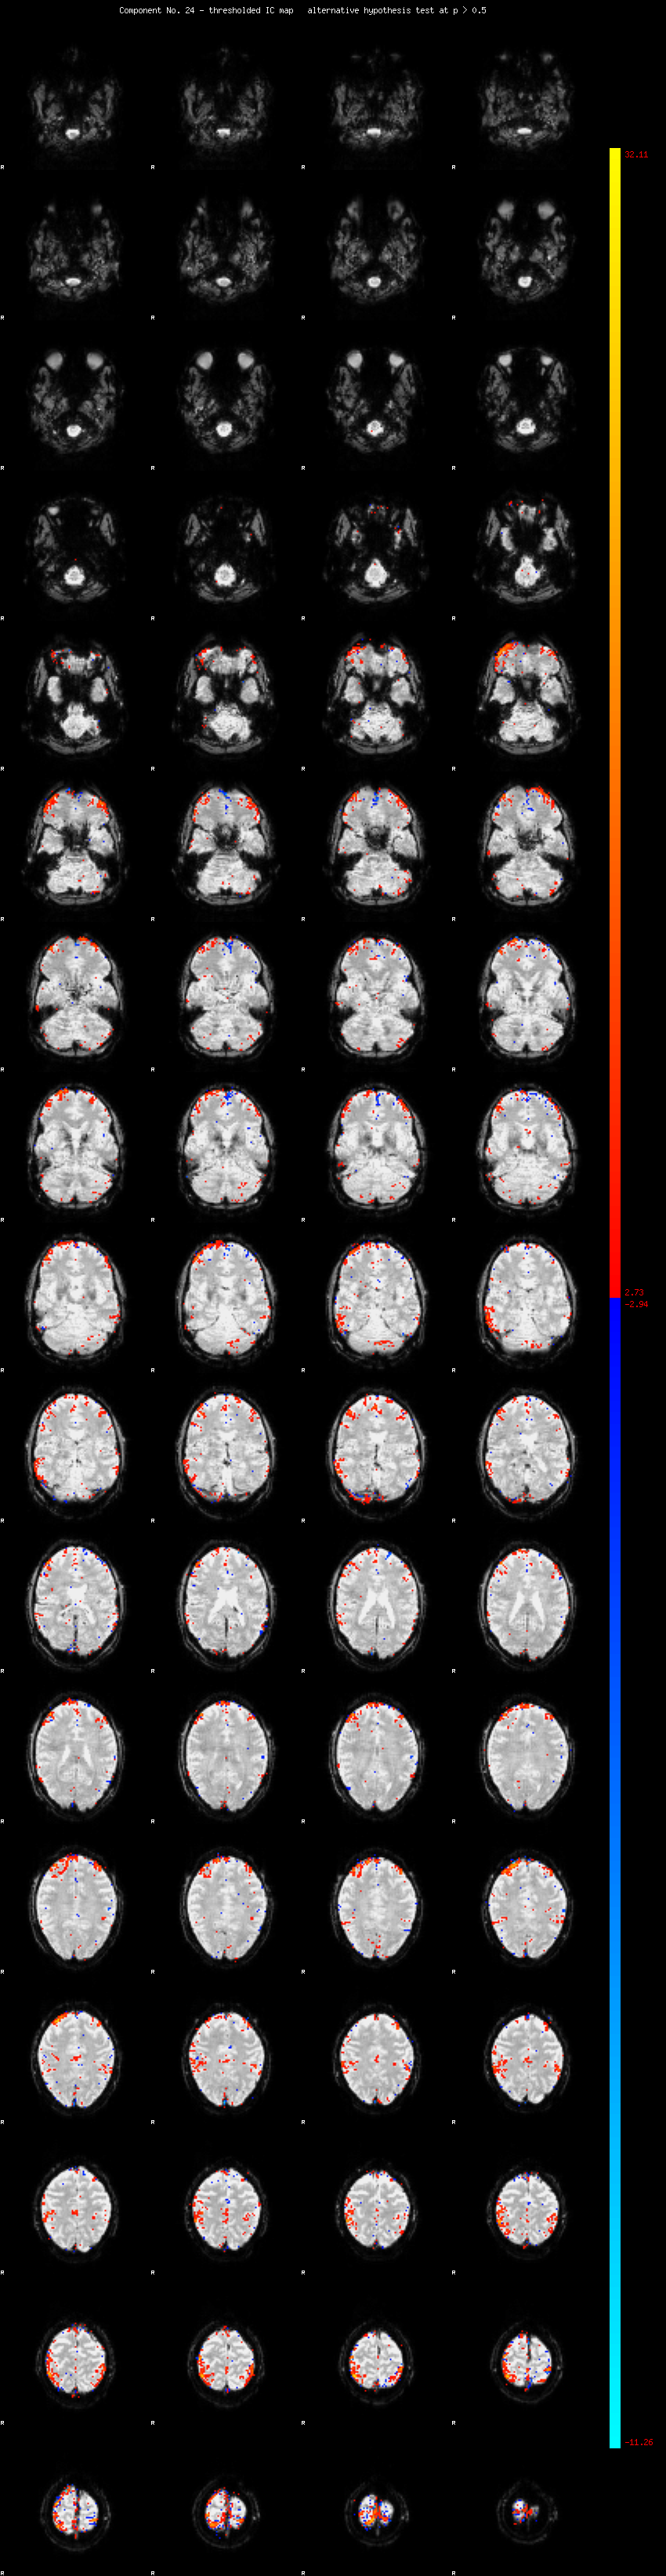

MELODIC Component 24

1.26 % of explained variance;     0.84 % of total variance

MMfit